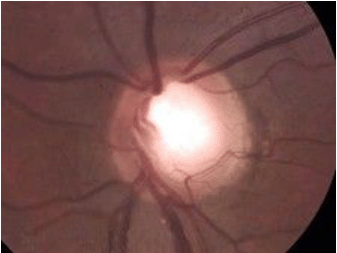

有关视神经缺损(如图)说法正确的是()

-

男性,47岁,诉右眼眼胀痛,查见眼底表现酷似一朵盛开的牵牛花,视盘比正常的扩大3~5倍,视盘周围有色素环及萎缩区,视盘呈漏斗状,眼底检查如图,对该病描述正确的是()